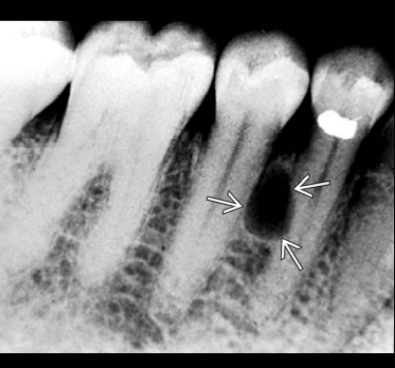

Οι περιακρορριζικές κύστεις είναι συνήθως ασυμπτωματικές και αποκαλύπτονται τυχαία κατά τη λήψη περιακρορριζικών ακτινογραφιών νεκρών οδόντων. Μια περιακρορριζική κύστη δεν μπορεί εύκολα να διακριθεί ακτινογραφικά από ένα περιακρορριζικό κοκκίωμα.

Σε κύστεις που υπάρχουν για αρκετό χρονικό διάστημα μπορεί να παρατηρηθεί απορρόφηση της ρίζας του υπεύθυνου δοντιού ή γειτονικών δοντιών. Οι περιακρορριζικές κύστεις θεωρούνται μια από τις συχνότερες, αν όχι η συχνότερη, αιτία εμφάνισης διόγκωσης στις γνάθους. Συχνά οι ασθενείς δίνουν ιστορικό παρουσίας χρόνιας, βραδέως αυξανόμενης διόγκωσης, η οποία αρχικά είναι σκληρής συστάσεως ανάλογης οστού. Καθώς η κύστη αυξάνεται, και παρά την εναπόθεση νέου οστίτη ιστού, το οστικό τοίχωμα της κύστης λεπταίνει βαθμιαία και η διόγκωση δίνει την εντύπωση κελύφους αυγού. Μόνο όταν ραγεί το οστικό τοίχωμα της κύστης μπορεί να παρατηρηθεί κλυδασμός. Στην άνω γνάθο η διόγκωση μπορεί να επεκτείνεται τόσο παρειακά όσο και υπερώια, ενώ κατά κανόνα στην κάτω γνάθο η διόγκωση επεκτείνεται παρειακά.

! Η ύπαρξη ενός νεκρού δοντιού είναι εξ’ ορισμού απαραίτητη για να τεθεί η διάγνωση της περιακρορριζικής κύστης.